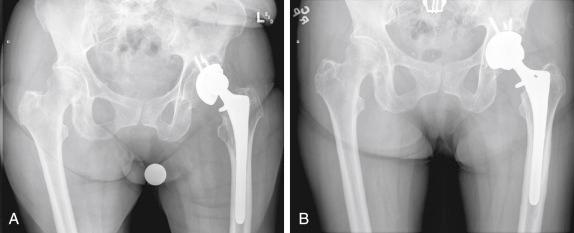

By definition, cavitary defects involve a volumetric loss of bone with preservation of the acetabular rim. Most cavitary defects can be managed with a hemispherical or elliptical acetabular component ( Fig. 54.1 ). The reconstruction is often combined with bone grafting or substitute material to fill the void. This allows the restoration of bone stock in case another revision is required, but it does not add to the initial stability of the construct.

FIGURE 54.1, A, Anteroposterior radiograph of the pelvis of an 83-year-old woman who presented with a loose acetabular component and with medial and superior cavitary defects. B, Postoperative radiograph shows a larger acetabular component with superior bone grafting.